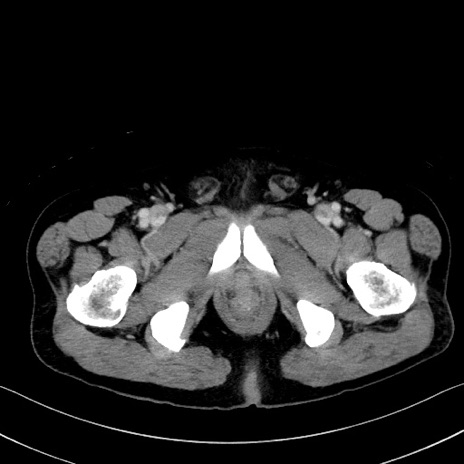

症例35(横断像)

【症例】70歳代 男性

【主訴】腹部膨満、嘔吐

【現病歴】昨日より腹部膨満感出現。本日増悪し、仙痛出現。嘔吐あり、受診。

【既往歴】糖尿病、胆摘後

【身体所見】BP 149/80mmHg、HR 74/min、BT 35.9℃、腹部:膨満、軟、圧痛なし。腸雑音減弱あり。上腹部正中切開瘢痕あり。

【データ】WBC 13500、CRP 1.72